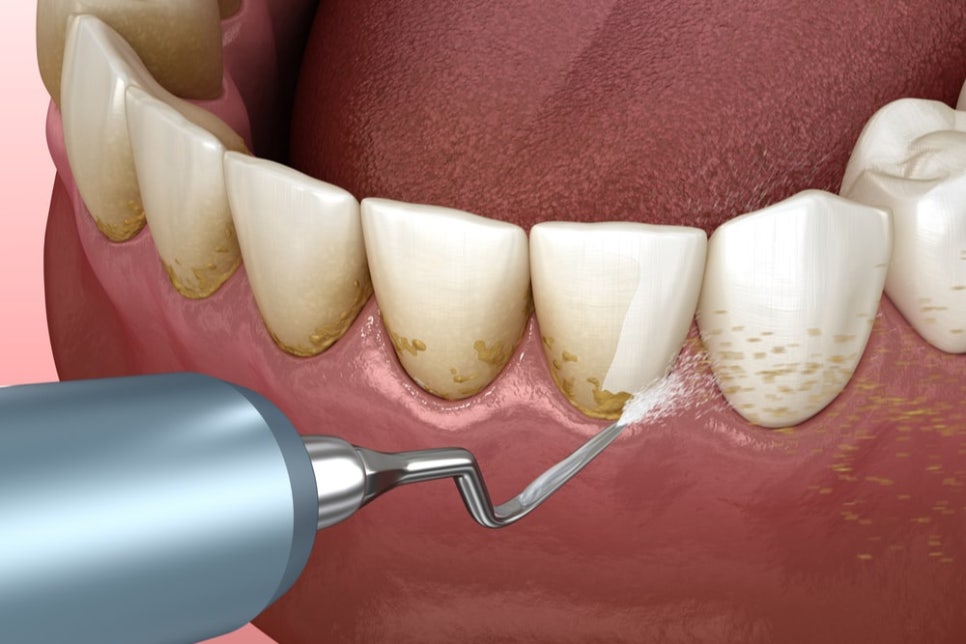

치주염을 일으키는 주범은

치아 뿌리에 단단하게 달라붙은 치석이에요.

치석은 세균들이 뭉쳐서 돌처럼

딱딱해진 덩어리인데,

아무리 좋은 약을 먹어도

이 돌덩이가 녹아서 사라지지는 않습니다.